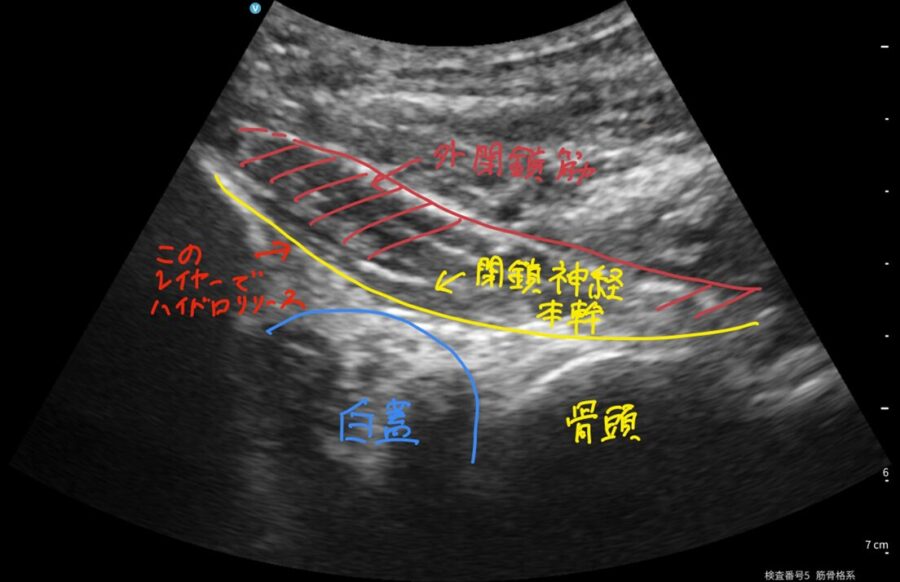

当院の治療:エコーガイド下「ハイドロリリース注射」

閉鎖神経が周りの組織に引っかかっている(滑りが悪い)ような場合、当院では エコーで神経や周囲を確認しながら、神経の周りに液体を注入して滑走性を改善する

エコーガイド下ハイドロリリース注射

を行い、神経の締めつけ(絞扼) にアプローチします。